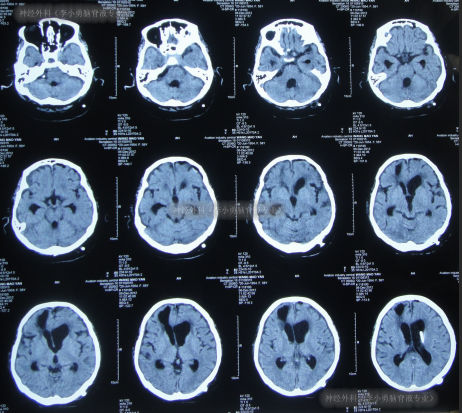

2012年6月14日,入院时:昏迷、体温很高、鼻饲、睡眠差,保留导尿(图-11)。入院后完善血、尿常规、生化全项、胸片、心电图等检查后病情危重,下病危通知。查头颅CT示脑积水(图-12)。

图-12:2012年6月14日头颅CT